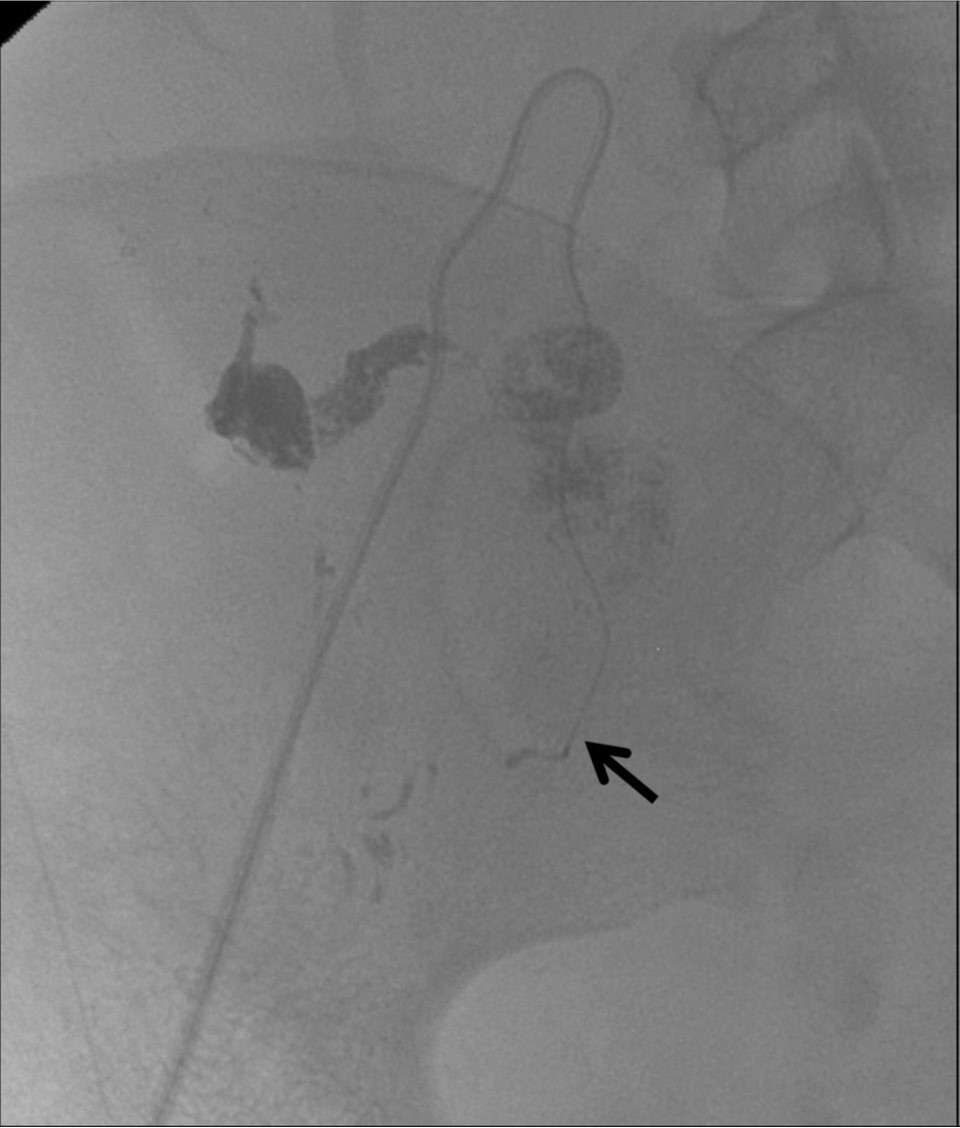

Fig. 2.

Pseudoaneurysm and extravasation spaces are filled with the mixture of NBCA and lipiodol during injection. Note the tip of a microcatheter in the proximal portion of the right uterine artery (arrow).